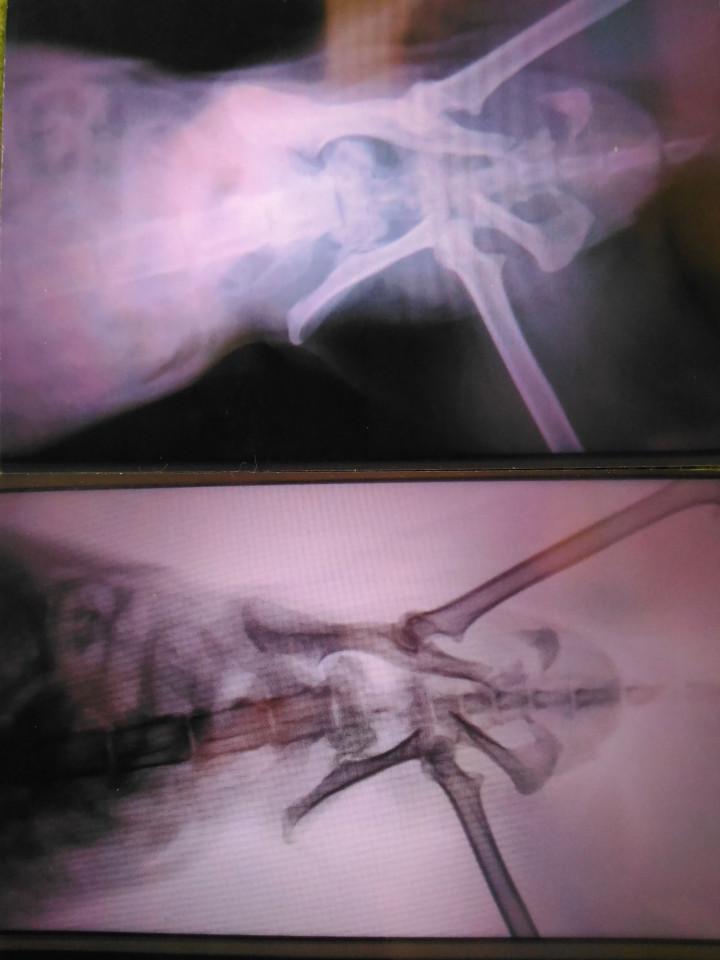

左(右も?)仙腸関節脱臼…

左後肢足根関節部を触るときしむ感じ

恥骨骨折 座骨骨折

右寛骨臼部骨折